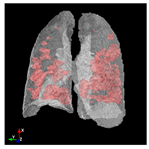

In Table 6, a comparison of the ground truth and prediction results of each model is presented in 2D, along with the 3D projection of each model. The visual analysis of the predictions provides additional insights into the performance of each model. The visualizations demonstrate that Attention UNet captures the intricate details of the lung construction more accurately, resulting in more precise segmentation of the infected areas compared to other models.

Table 6.

Comparison of ground truth and model prediction results using UNet, LinkNet, Attention UNet, UNet 3+, and TransUNet.

Attention UNet stands out due to its sophisticated attention mechanisms that allow it to focus on relevant regions and features within the lung structures. This characteristic enhances its ability to capture intricate details specific to COVID-19-affected lungs. The attention mechanisms contribute to Attention UNet’s impressive IoU score of 85.36% and dice score of 91.49%, showcasing its potential to provide accurate and finely detailed segmentations. The results suggest that its trait of dynamically assigning different weights to regions, based on their contextual importance, is instrumental in achieving precise and meaningful segmentations in complex medical images.